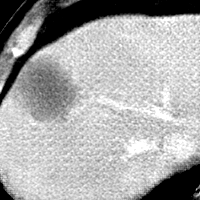

Refer to caption

CT

Zoomed

MRI

Target\mathrm{Target}

StolenEPD{\mathrm{Stolen}}^{\mathrm{D}}_{\mathrm{EP}}

StolenEPD1{\mathrm{Stolen}}^{\mathrm{D1}}_{\mathrm{EP}}

StolenITD{\mathrm{Stolen}}^{\mathrm{D}}_{\mathrm{IT}}

StolenITD1{\mathrm{Stolen}}^{\mathrm{D1}}_{\mathrm{IT}}

Figure 7: Lossy image reconstructions on CT (row 1, 2) and MRI (row 3, 4) images, where the row 2, 4 provide a zoomed-in view of the bounding box region of the row 1, 3. The leftmost column represents the target images, while the subsequent four columns show the stolen images reconstructed by the decoder D or D1 in two scenarios.

A visual comparison between target and stolen images is available in Fig. 7. We observe that the stolen images from IT Scenario closely resemble the input ones, particularly in the tumor regions, whereas stolen images from EP Scenario exhibit blurring artifacts in finer details. In both cases, the stolen images reconstructed by D1D1 demonstrate a comparable quality to those reconstructed by DD, thus further confirming the effectiveness of the reduced decoder D1D1.